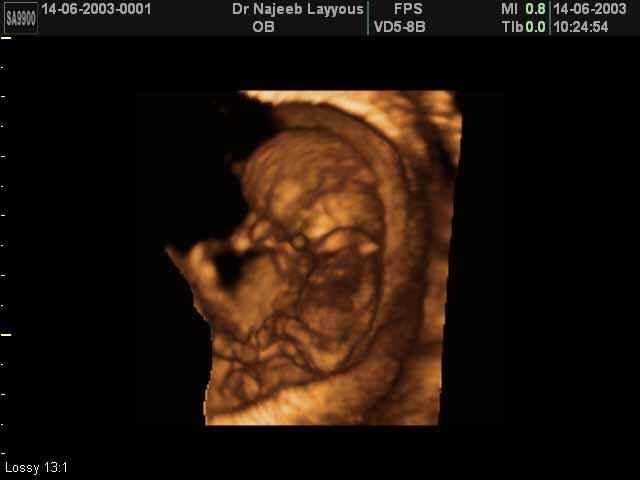

- First Trimester Ultrasound Photos

3D First Trimester Ultrasound Scan Photos ( Early Pregnancy Ultrasound Photos ) | Dr N Layyous